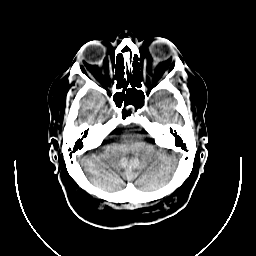

CT Study #1 -- Slice #6

[Home][Help][Clinical][Tour 1] Slice 6